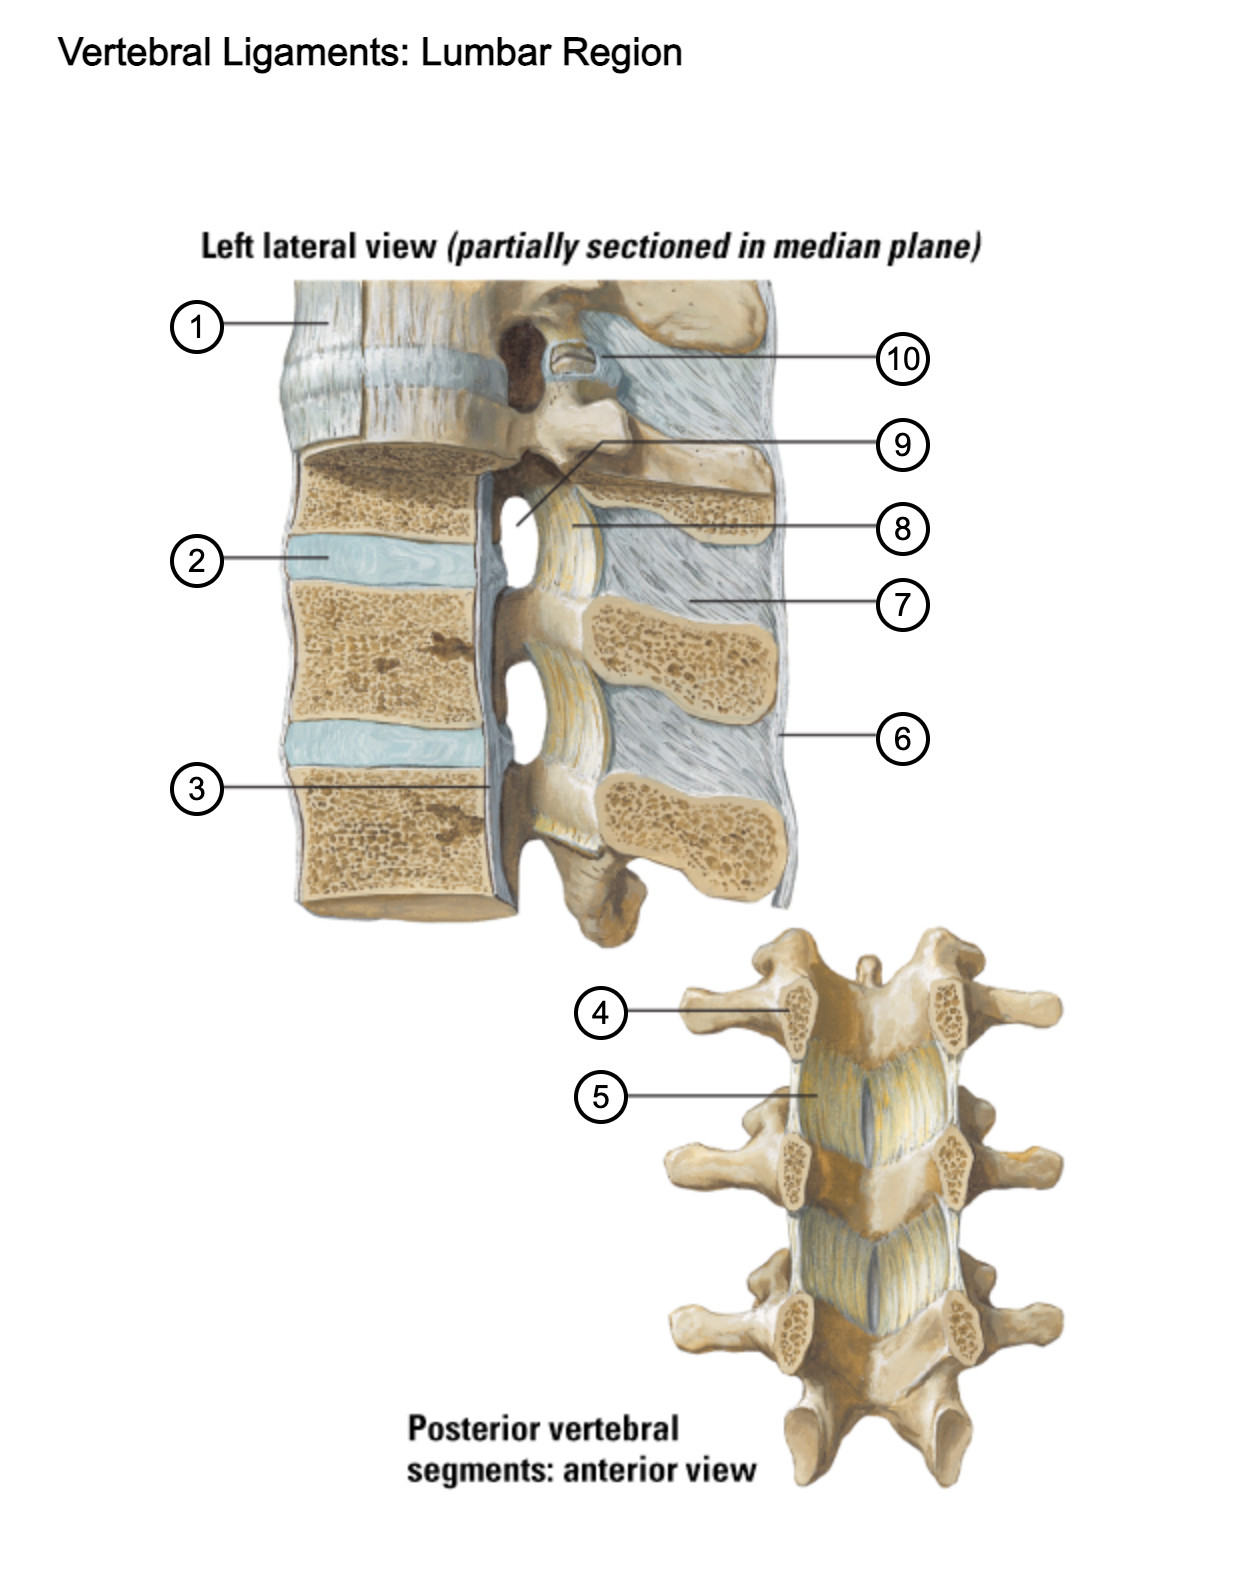

1

anterior longitudinal ligament

2

intervertebral disc

3

posterior longitudinal ligament

4

pedicle (cut surface)

5

ligamentum flavum

6

supraspinous ligament

7

interspinous ligament

8

ligamentum flavum

9

intervertebral foramen

10

capsule of zygapophysial join (partially opened)